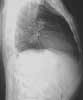

You order frontal and lateral uprightradiographs of the chest. Whatabnormalities are evident on thesefilms, and how will you proceed todetermine their cause?

Thefrontal (

A

) and lateral (

B

) radiographsreveal ill-defined opacities inthe middle and upper lobes of theright lung (

A and B, white arrows

)and thickening in the right apex (

A,yellow arrow

).You order a CT scan of thechest. An axial image at the level ofthe middle third of the left ventricleshows an opacity in the superior segmentof the right lower lobe (